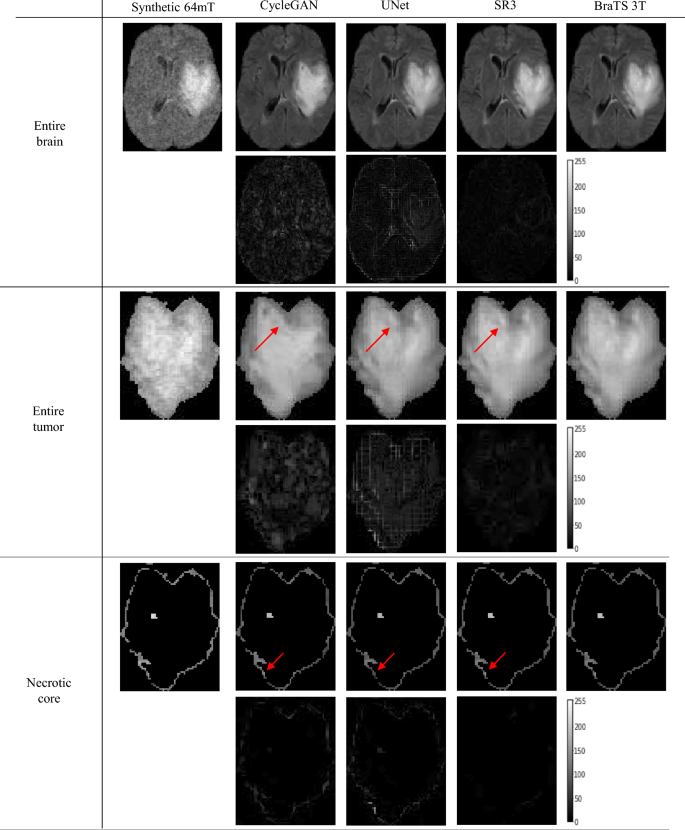

Figure 4 shows one example from the N = 500 tested subset; each one of the six panels includes the synthetic 64mT FLAIR (upper left), the inference outcomes for the three tested models (columns two to five) followed by the corresponding BraTS 3T FLAIR (the ground truth from which the synthetic 64mT was generated). In each panel the second row is the pixel-to-pixel difference between the inference outcome and the ground truth 3T. According to Fig. 4, the SR3 model consistently demonstrates better tumor enhancement across all tissue types. This is also evident in the error maps, i.e., difference enhanced minus ground truth, SR3 outperforms other models in accurately capturing the characteristics of all tumor types. Please note that the error maps are presented with increased brightness (50% increase; pixel values multiplied by 1.5) to emphasize the degree of differences. The performance of the SR3 can be appreciated, for example, in the contrast–agent enhanced potion of the tumor. As highlighted by the arrows that point to significant areas of enhancement, the border of the contrast-enhanced core is better outlined in the SR3-enhanced images. These findings on the enhancing tumor regions showcase SR3’s ability to maintain low error despite complex textures. The error maps also reveal that SR3 achieves lower errors in healthy tissue and whole-brain reconstructions as well, preserving anatomical details more precisely than UNet and CycleGAN.

Representative outcomes from a test inference on a FLAIR image from the BraTS dataset. Arrows highlight areas with significant differences for each analyzed tissue. The pixel intensity of the error maps has been increased by 50% (multiplying the pixel values by a factor of 1.5) to improve error visibility.